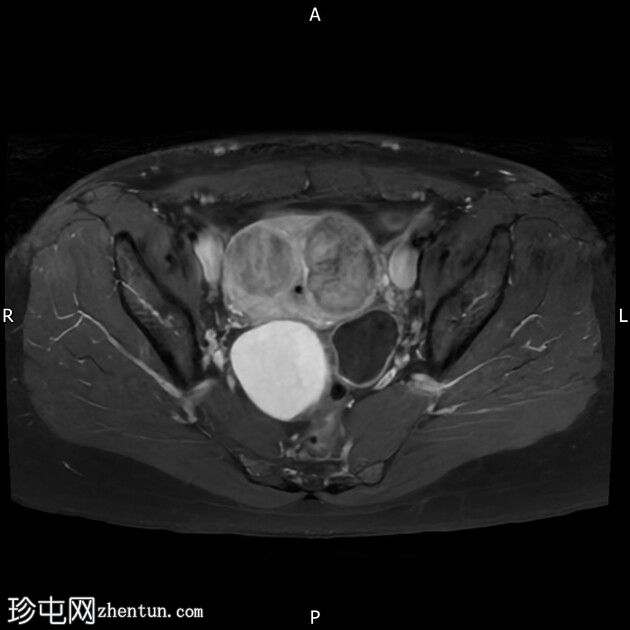

轴位

T2加权像

右侧卵巢囊肿,T2加权像呈低信号,T1脂肪抑制像呈高信号,大小为6 x 5.2 cm,符合子宫内膜异位囊肿的影像学表现。

左侧卵巢囊肿,T2加权像呈低信号,T1脂肪抑制像呈高信号,符合子宫内膜异位囊肿的影像学表现。

双侧卵巢粘连于后道格拉斯窝,呈“接吻卵巢征”。

结论:双侧卵巢子宫内膜异位囊肿。多发性子宫肌瘤。

本病例显示右侧卵巢子宫内膜异位症,左侧卵巢囊肿内含出血性物质,并可见“接吻卵巢征”,诊断为卵巢子宫内膜异位囊肿伴可能粘连/深部盆腔子宫内膜异位症。